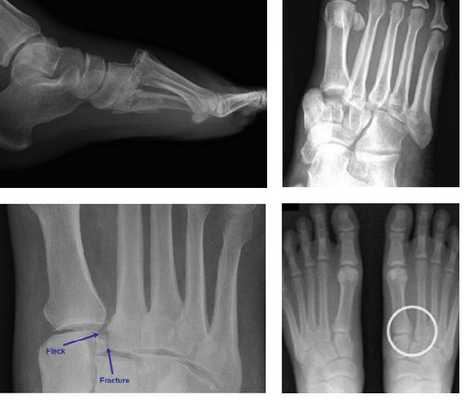

Рис. 5. Схема костного дефекта при дезинтеграции сустава Шопара

Рис. 6. Отрывной перелом по тылу таранной кости на границе с суставом Шопара

Рис. 7. Перелом кубовидной кости по передней поверхности

Рис. 8. Переломо-вывих в суставе Шопара

Рис. 9. Переломо-вывих в суставе Шопара